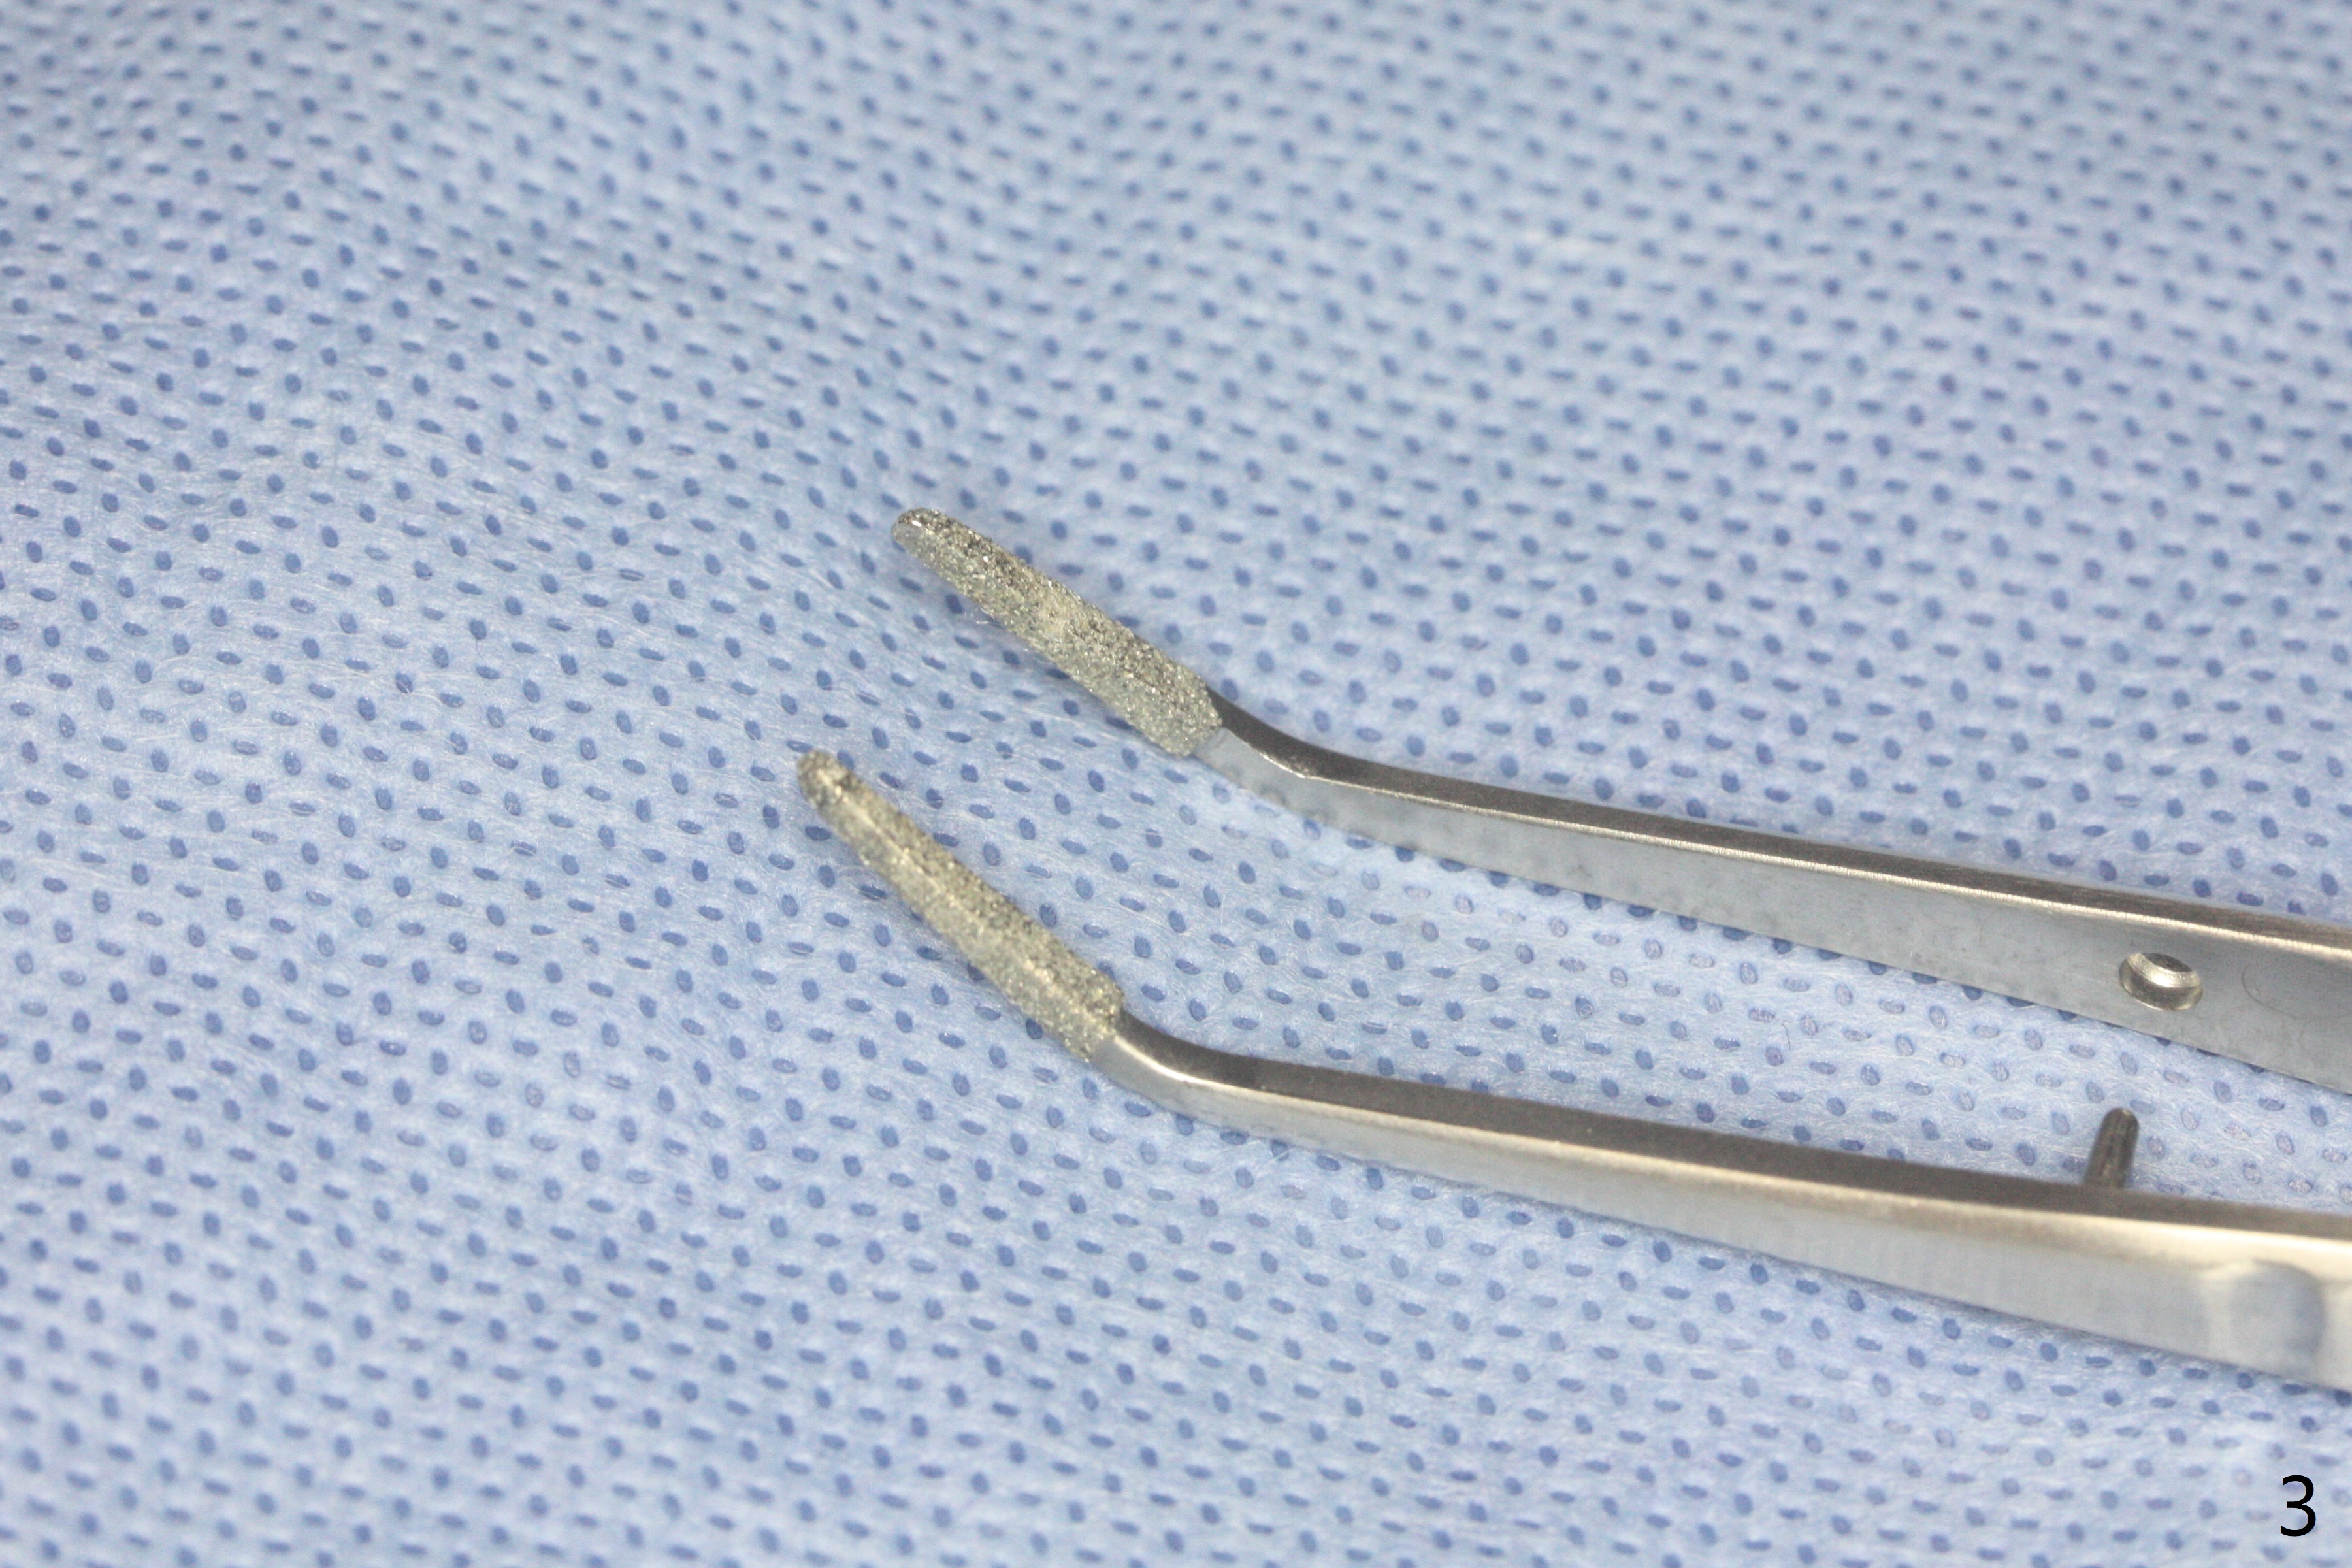

53岁黑男要求拔除松动,剧烈疼痛的左上7(图一(*:上颌窦底板)),同意植骨,分期付款。拔牙后牙槽窝硕大,有许多难以刮除的肉芽组织,出血多,颊侧骨壁应该缺失。在放置GEM21S人工合成骨和异体骨(主要部分)前,在牙槽窝深部放置两个Osteogen塞(图二:P,止血,所谓胶原骨,另外一种人工合成骨),覆盖不可吸收膜,PTFE缝线,间隙保持器,牙周敷料。由于对合牙是智齿,垂直高度有限,放置保持器和敷料有困难。去除炎性肉芽组织,使用两个大小不太带齿刮匙,血管钳,特殊镊子以及带金刚石镊子(图三),反复多次使用自配生理盐水(图四)冲洗。